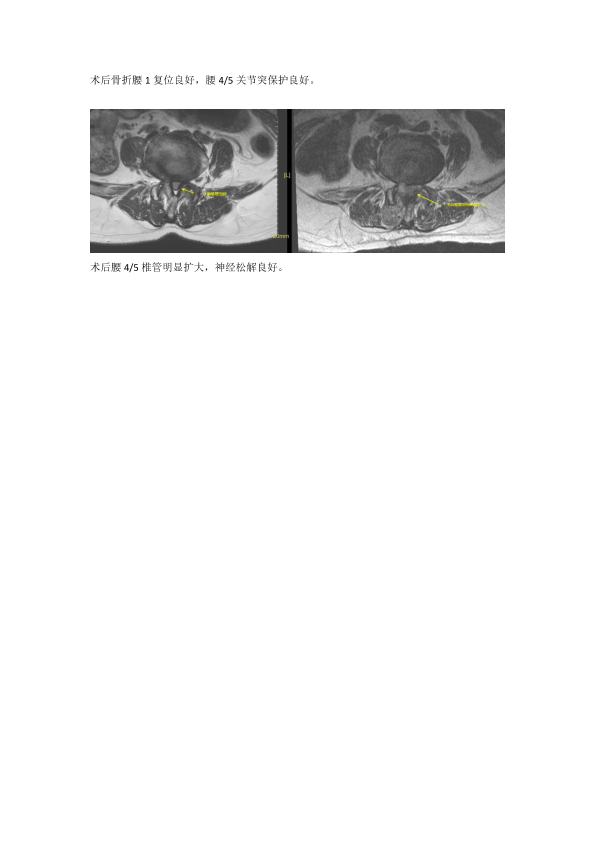

微创巧妙化解患者新伤和旧疾